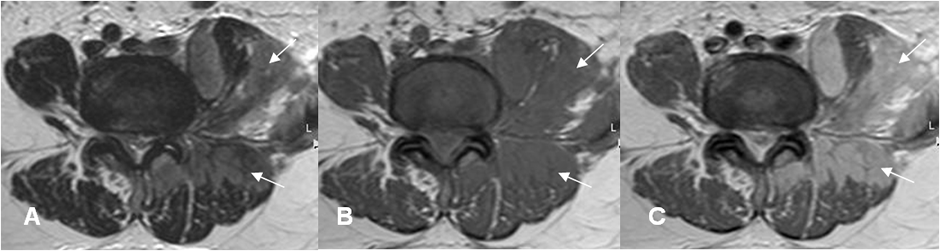

Fig 186 B. Linfoma.

A: RM axial en T2, B: RM axial en T1 simple y C: RM axial en T1 con contraste. Igual paciente anterior. Infiltración de los músculos psoas y paraespinales del lado izquierdo, que realzan con el contraste, por linfoma.

Fig 186 C. Linfoma.

A: RM sagital en T1. Igual paciente anterior. Infiltración del cuerpo de L5. (Flecha gruesa). El canal medular está ocupado, por tejido blando. (Flechas delgadas).

B: RM sagital y C: RM coronal en T1 con contraste. Realce heterogéneo del contraste, en L5. La masa de tejidos blandos paravertebral izquierda se extiende al canal medular y rodea el saco dural.